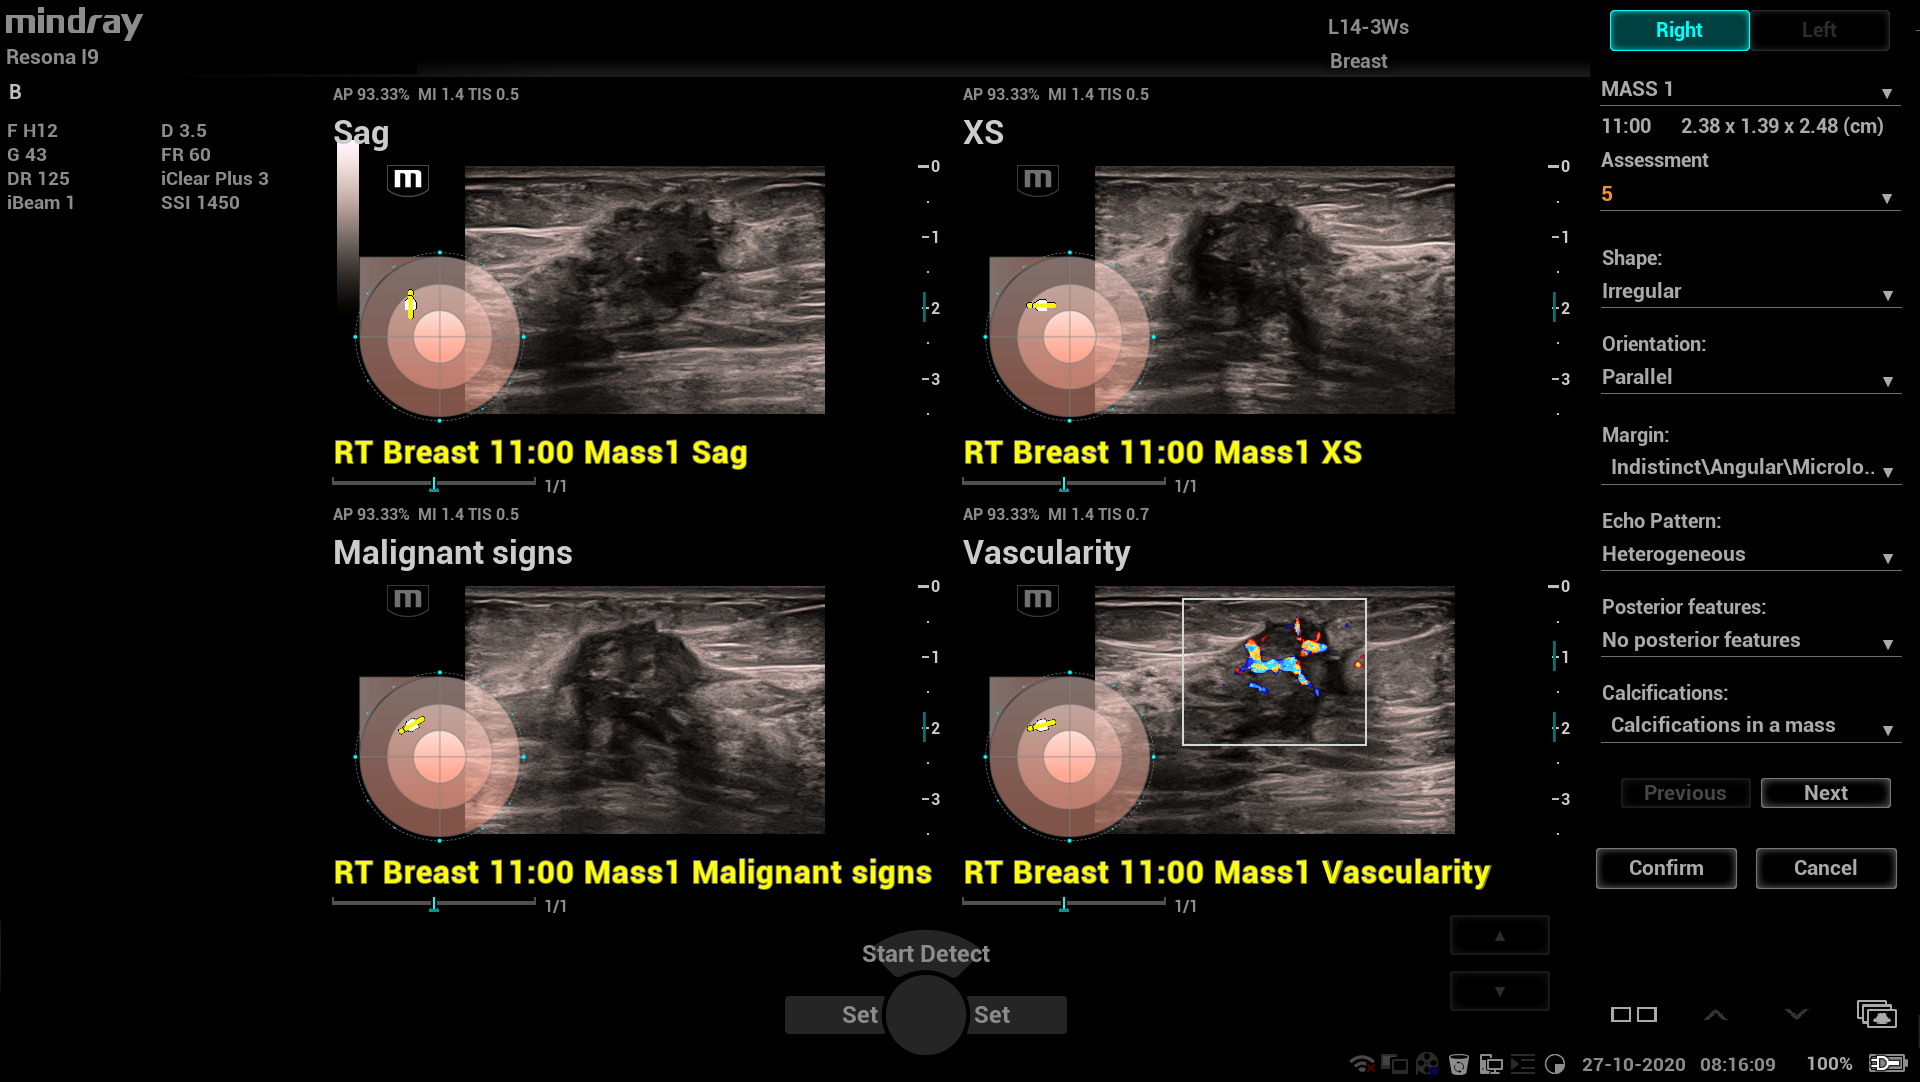

-Smart Breast - умная и точная диагностика молочной железы. Интеллектуальный анализ BI-RADS обеспечивает полностью автоматическое обнаружение поражений, измерение, аннотирование, анализ и составление отчётов. Протокол сканирования, ориентированный на очаги поражения, эффективно улучшает контроль качества. Кроме того, систематическое лечение множественных пораженийи оценка в нескольких плоскостях дополнительно предоставляют больше диагностической информации и большую точность.